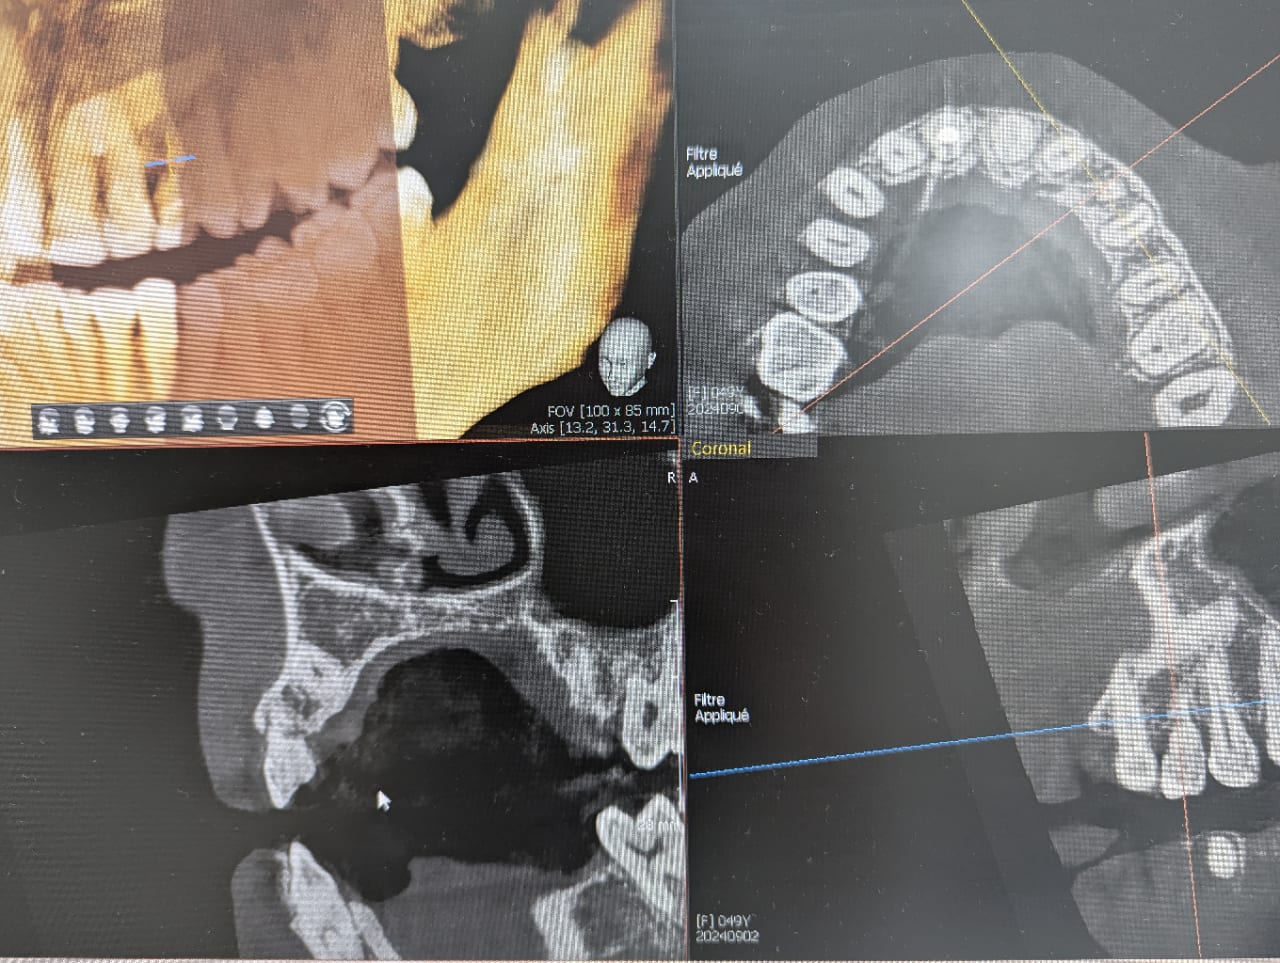

patiente dont la canine de lait 63 est devenue mobile ( je me demande s il n y a pas une fracture au niveau de la racine) et la canine incluse couchée à 90 degré occupe tout le volume osseux de la corticale externe à la corticale interne sous la 63. l option bridge collé pour remplacer la dent ne me parait pas trop viable dans le temps.

Par voie vestibulaire ou palatine, il faudrait plus de coupes pour décider.

Image de la canine plus grosse = position palatine à 100%

Elle se situe juste derrière les incisives

La seule difficulté, décoller la muqueuse palatine….

Après quand on voit cette coupe cbct, je ne suis pas certain que l’extraction soit une partie de plaisir.

sur les autres coupes la couronne est en palatin et l apex en vestibulaire, la dent occupe vraiment une grosse partie du volume osseux de de la crête .